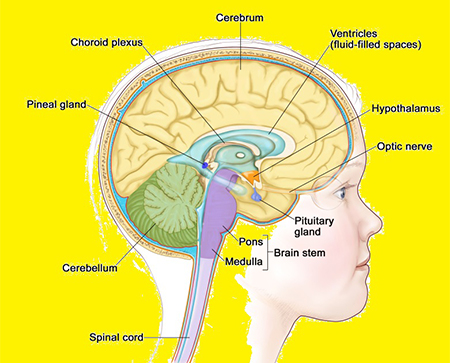

غده صنوبری که به عنوان غده کاجی یا غده پینهآل نیز شناخته می شود، یک غده درون ریز کوچک است که در مرکز مغز قرار دارد. غده صنوبری علیرغم اندازه کوچکش، نقش مهمی در تنظیم فرآیندهای فیزیولوژیکی مختلف در بدن از جمله چرخه خواب و بیداری، خلق و خو و رشد جنسی دارد.

غده صنوبری به شکل مخروط کاج است و به اندازه یک نخود است و قطر آن تقریباً 8 میلی متر است. در اپیتالاموس، ناحیه ای از مغز که بین دو نیمکره قرار دارد و توسط تالاموس احاطه شده است، قرار دارد. غده صنوبری از پینهآلوسیتها تشکیل شده است که سلولهای تخصصی هستند که ملاتونین، هورمونی که چرخه خواب و بیداری را تنظیم میکند، تولید و ترشح میکنند.

تولید ملاتونین توسط بخشی از مغز به نام هسته سوپراکیاسماتیک (SCN) که در هیپوتالاموس قرار دارد، کنترل می شود. SCN اطلاعات مربوط به چرخه های نور و تاریکی را از چشم دریافت می کند و سیگنال هایی را برای تنظیم تولید ملاتونین به غده صنوبری ارسال می کند. در طول روز، زمانی که نور بیشتری وجود دارد، SCN سیگنال هایی را برای سرکوب تولید ملاتونین ارسال می کند. در شب، زمانی که نور کمتری وجود دارد، SCN سیگنال هایی را برای تحریک تولید ملاتونین ارسال می کند که به بهبود خواب کمک می کند.

غده صنوبری علاوه بر نقشی که در تنظیم چرخه خواب و بیداری دارد، در تنظیم خلق و خو و رشد جنسی نیز نقش دارد. مطالعات نشان داده اند که افراد مبتلا به افسردگی و سایر اختلالات خلقی سطوح پایین تری از ملاتونین دارند که نشان می دهد غده صنوبری ممکن است در این شرایط نقش داشته باشد. غده صنوبری همچنین با تولید سطوح بالاتر ملاتونین در دوران کودکی و سطوح پایین تر در دوران نوجوانی به تنظیم شروع بلوغ کمک می کند.

غده صنوبری با تنظیم تولید هورمون هایی که در شروع بلوغ نقش دارند در رشد جنسی نقش دارد . به طور خاص، غده صنوبری هورمون ملاتونین را تولید و ترشح می کند که در تنظیم محور تولید مثل نقش دارد.

در دوران کودکی، غده صنوبری سطوح بالایی ملاتونین تولید می کند که از تولید هورمون آزاد کننده گنادوتروپین ( GnRH ) در هیپوتالاموس جلوگیری می کند. GnRH هورمونی است که باعث ترشح هورمون لوتئینیزه کننده (LH) و هورمون محرک فولیکول (FSH) از غده هیپوفیز می شود که به نوبه خود تولید استروژن و تستوسترون را در تخمدان ها و بیضه ها تحریک می کند.

با کاهش سطح ملاتونین در دوران نوجوانی، مهار تولید GnRH برداشته میشود و به تولید LH و FSH اجازه میدهد تا افزایش یابد و شروع بلوغ را آغاز کند. این منجر به تولید هورمون های جنسی می شود که مسئول ایجاد ویژگی های جنسی ثانویه مانند رشد سینه در زنان و رشد موهای صورت در مردان هستند.